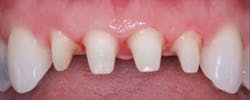

Figure 4: Patient with splinted anterior crowns and large carious lesion on lateral incisor had moderate constant pain

Figure 5: Patient had moderate postoperative pain after tooth preparation appointment.